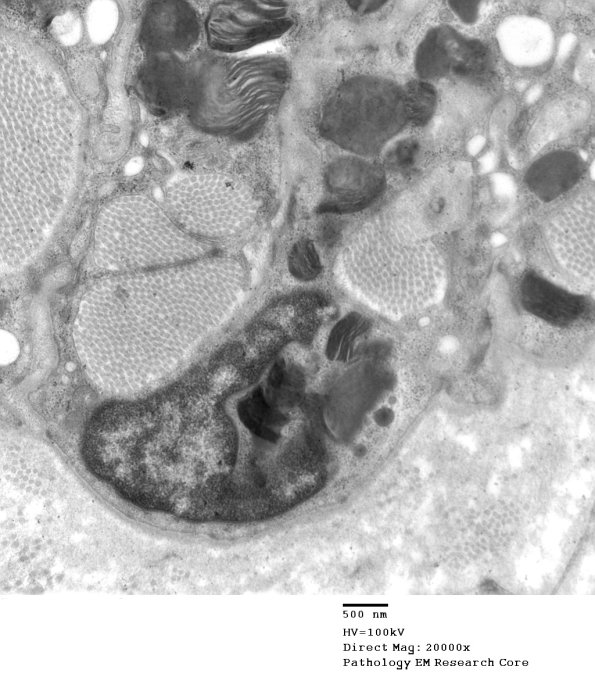

Increasing magnifications of the macrophage inclusions show delicate microlamellar appearance. (electron micrographs)